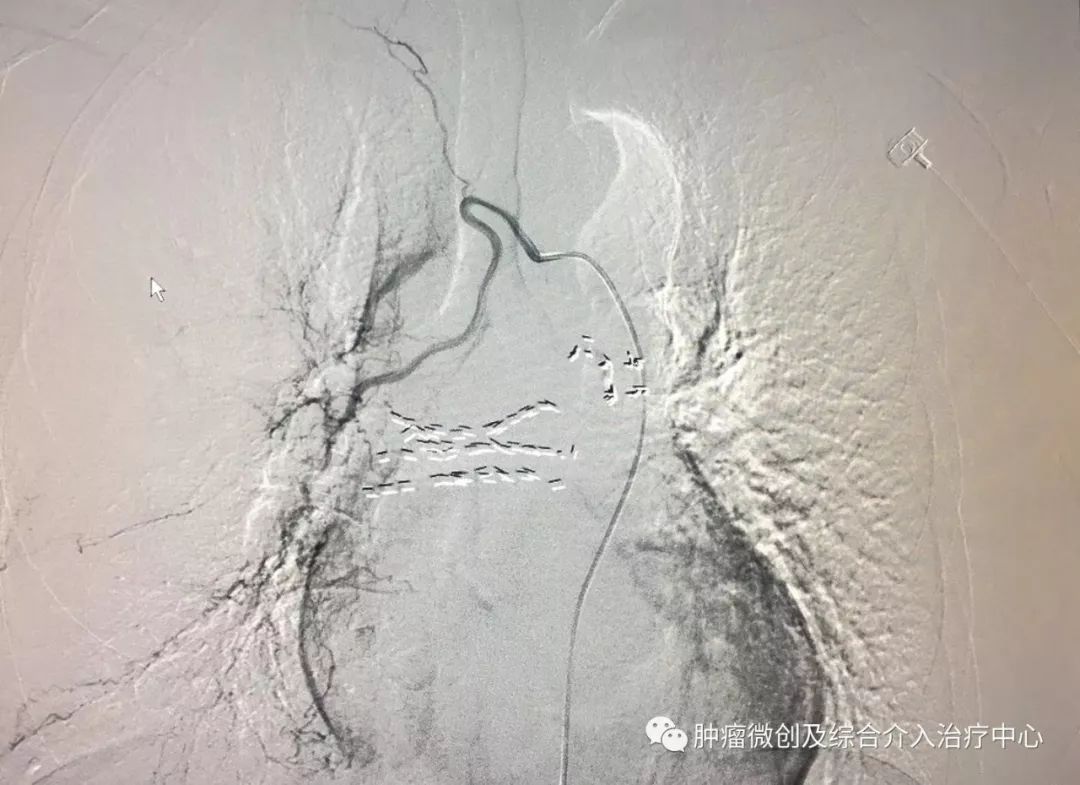

(肺动脉造影提示左肺动脉部分分支血管未显影,血栓形成,患者呼吸困难,胸闷、胸痛)

(经肺动脉导管溶栓治疗后,左肺动脉及其分支血管显影清晰,大部血栓溶解,患者呼吸困难症状改善,无胸闷及胸痛症状。)